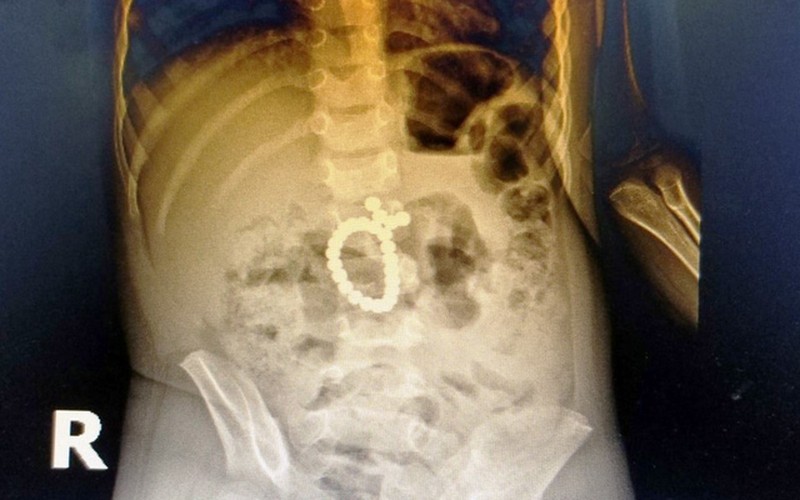

Ngay sau khi tiếp nhận, qua các xét nghiệm và X-quang ổ bụng bệnh nhi, các bác sĩ đã phát hiện bệnh nhân bị tắc ruột do dị vật hình tròn, bao gồm nhiều viên nhỏ và dính thành chuỗi. Các bác sĩ khoa Ngoại và khoa Gây mê hồi sức tiến hành hội chẩn và chỉ định mổ cấp cứu.

Trong quá trình phẫu thuật, các bác sĩ đã phát hiện 25 viên bi nam châm dính chặt vào nhau gây tắc nghẽn ruột, khiến tá tràng và ruột bệnh nhi thủng nhiều vị trí. Sau gần 3 giờ, các phẫu thuật viên đã loại bỏ hoàn toàn dị vật, khâu kín vị trí ruột thủng thành công.

25 viên bi nam châm dính chặt vào nhau gây tắc nghẽn ruột, khiến tá tràng và ruột bệnh nhi thủng nhiều vị trí. (Ảnh: Yến Phương)